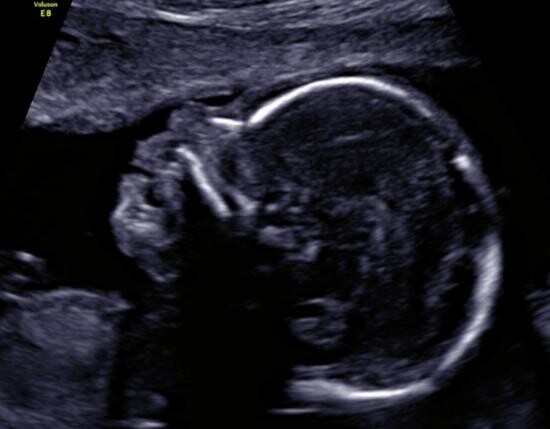

- badanie I trymestru (USG + test II z krwi matki) wykonywane między 11-14 t.c.

Celem badań jest wykrywanie wad wrodzonych u płodu, oszacowanie ryzyka wystąpienia nieprawidłowości chromosomowych u płodu na podstawie tzw. markerów.